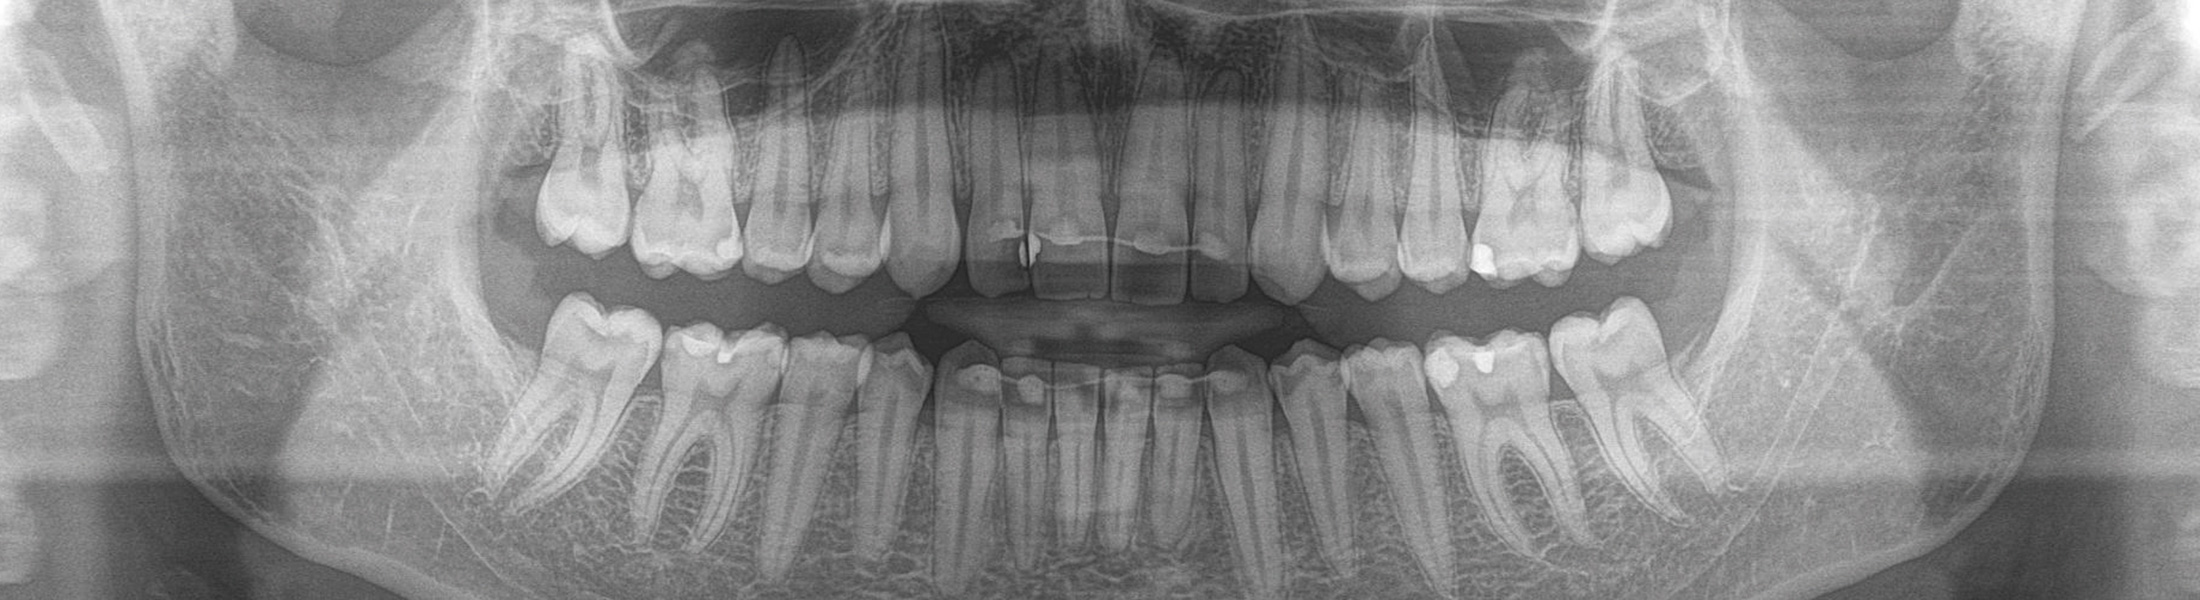

Wir nutzen innovative Diagnosetechniken. Detaillierte, umfassende Diagnosen sind die Grundlage, um Planung und Behandlung so präzise wie möglich zu gestalten. Mit digitaler, strahlungsarmer Röntgentechnik erhalten wir genaue Informationen zur Knochensituation und -qualität. Ausführliche Diagnostik und präzise prä- und postoperative Planung bilden die Basis für eine medizinisch sinnvolle Therapie und unterstützen vor und während des Eingriffs.

Wenn die klassische Diagnostik keine eindeutigen Ergebnisse liefert, lassen wir mit einem Digitalen Volumentomographen (DVT) eine detailliertere, 3-dimensionale Diagnostik erstellen. Mit den gestochen scharfen 3-D-Ansichten können die knöchernen Strukturen des Oberkiefers und des Unterkiefers, ausgesuchte, einzelne Segmente oder komplexe Zusammenhänge detailliert dargestellt und analysiert werden. Es können Befunde diagnostiziert werden, die oft mit konventionellen Aufnahmetechniken nicht erkennbar sind.

Diese neue Technik der digitalen Volumentomographie eröffnet der Zahnmedizin heute zuverlässige diagnostische und therapeutische Möglichkeiten in der Implantologie, Prothetik, Kieferorthopädie und Zahnerhaltung.